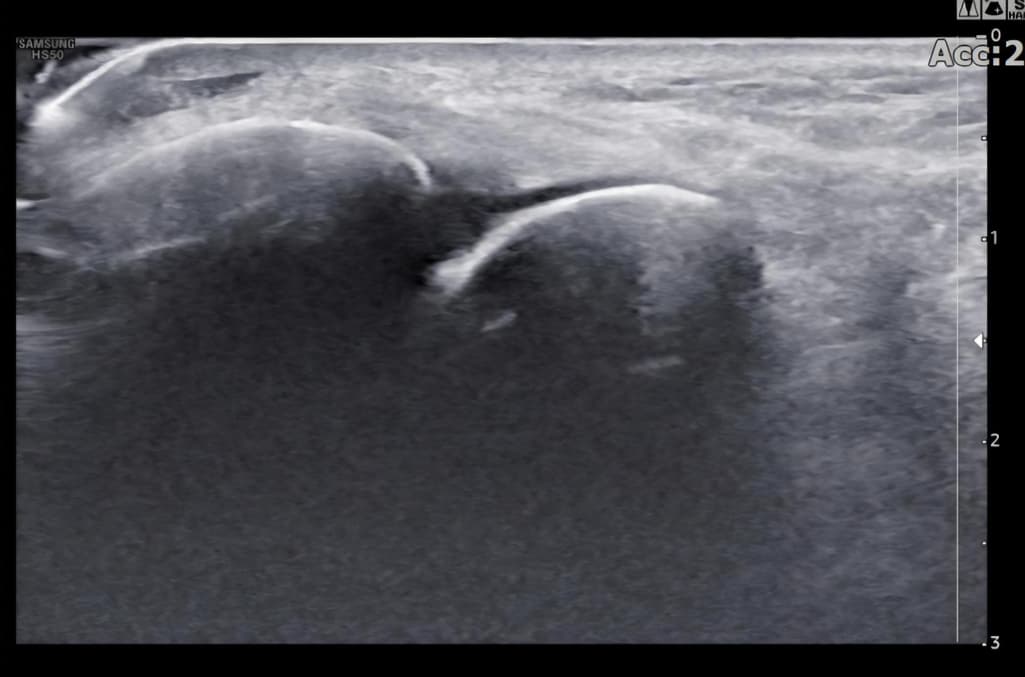

그런데 다친 지 2주 뒤부터 발목이 쑤시듯 아파 병원에서 초음파 검사를 했고, 전거비인대(ATFL) 2도 염좌 진단을 받았습니다. 이후 약 6주 동안 주 1회씩 충격파, 물리치료, 도수치료 등을 받았습니다. (고정치료는 시기가 늦었다며 진행하지 않았습니다.)

그리고, 처음 초음파 사진(6월 촬영)과 비교하여

mri 사진(8월 촬영)상 인대가 호전됬는지도

알고 싶습니다.

초음파와 비교하면 mri 상으로 인대 연속성이 확인되므로 심각한 악화나 재파열은 아닌 것으로 판단됩니다